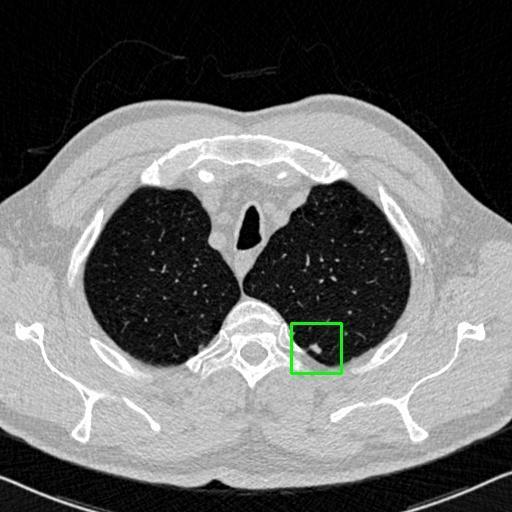

We developed an AI-based system using deep learning models for analyzing lung CT scans to detect and classify pulmonary nodules. We chose the YOLOv11 architecture for its enhanced object detection capability and adapted it specifically for medical imaging, incorporating pixel-level precision and severity classification.

Classification into three severity levels with colored bounding boxes.

Designed a severity classification system that categorizes nodules into null, moderate, and severe using colored bounding boxes, assisting in rapid clinical decision-making.